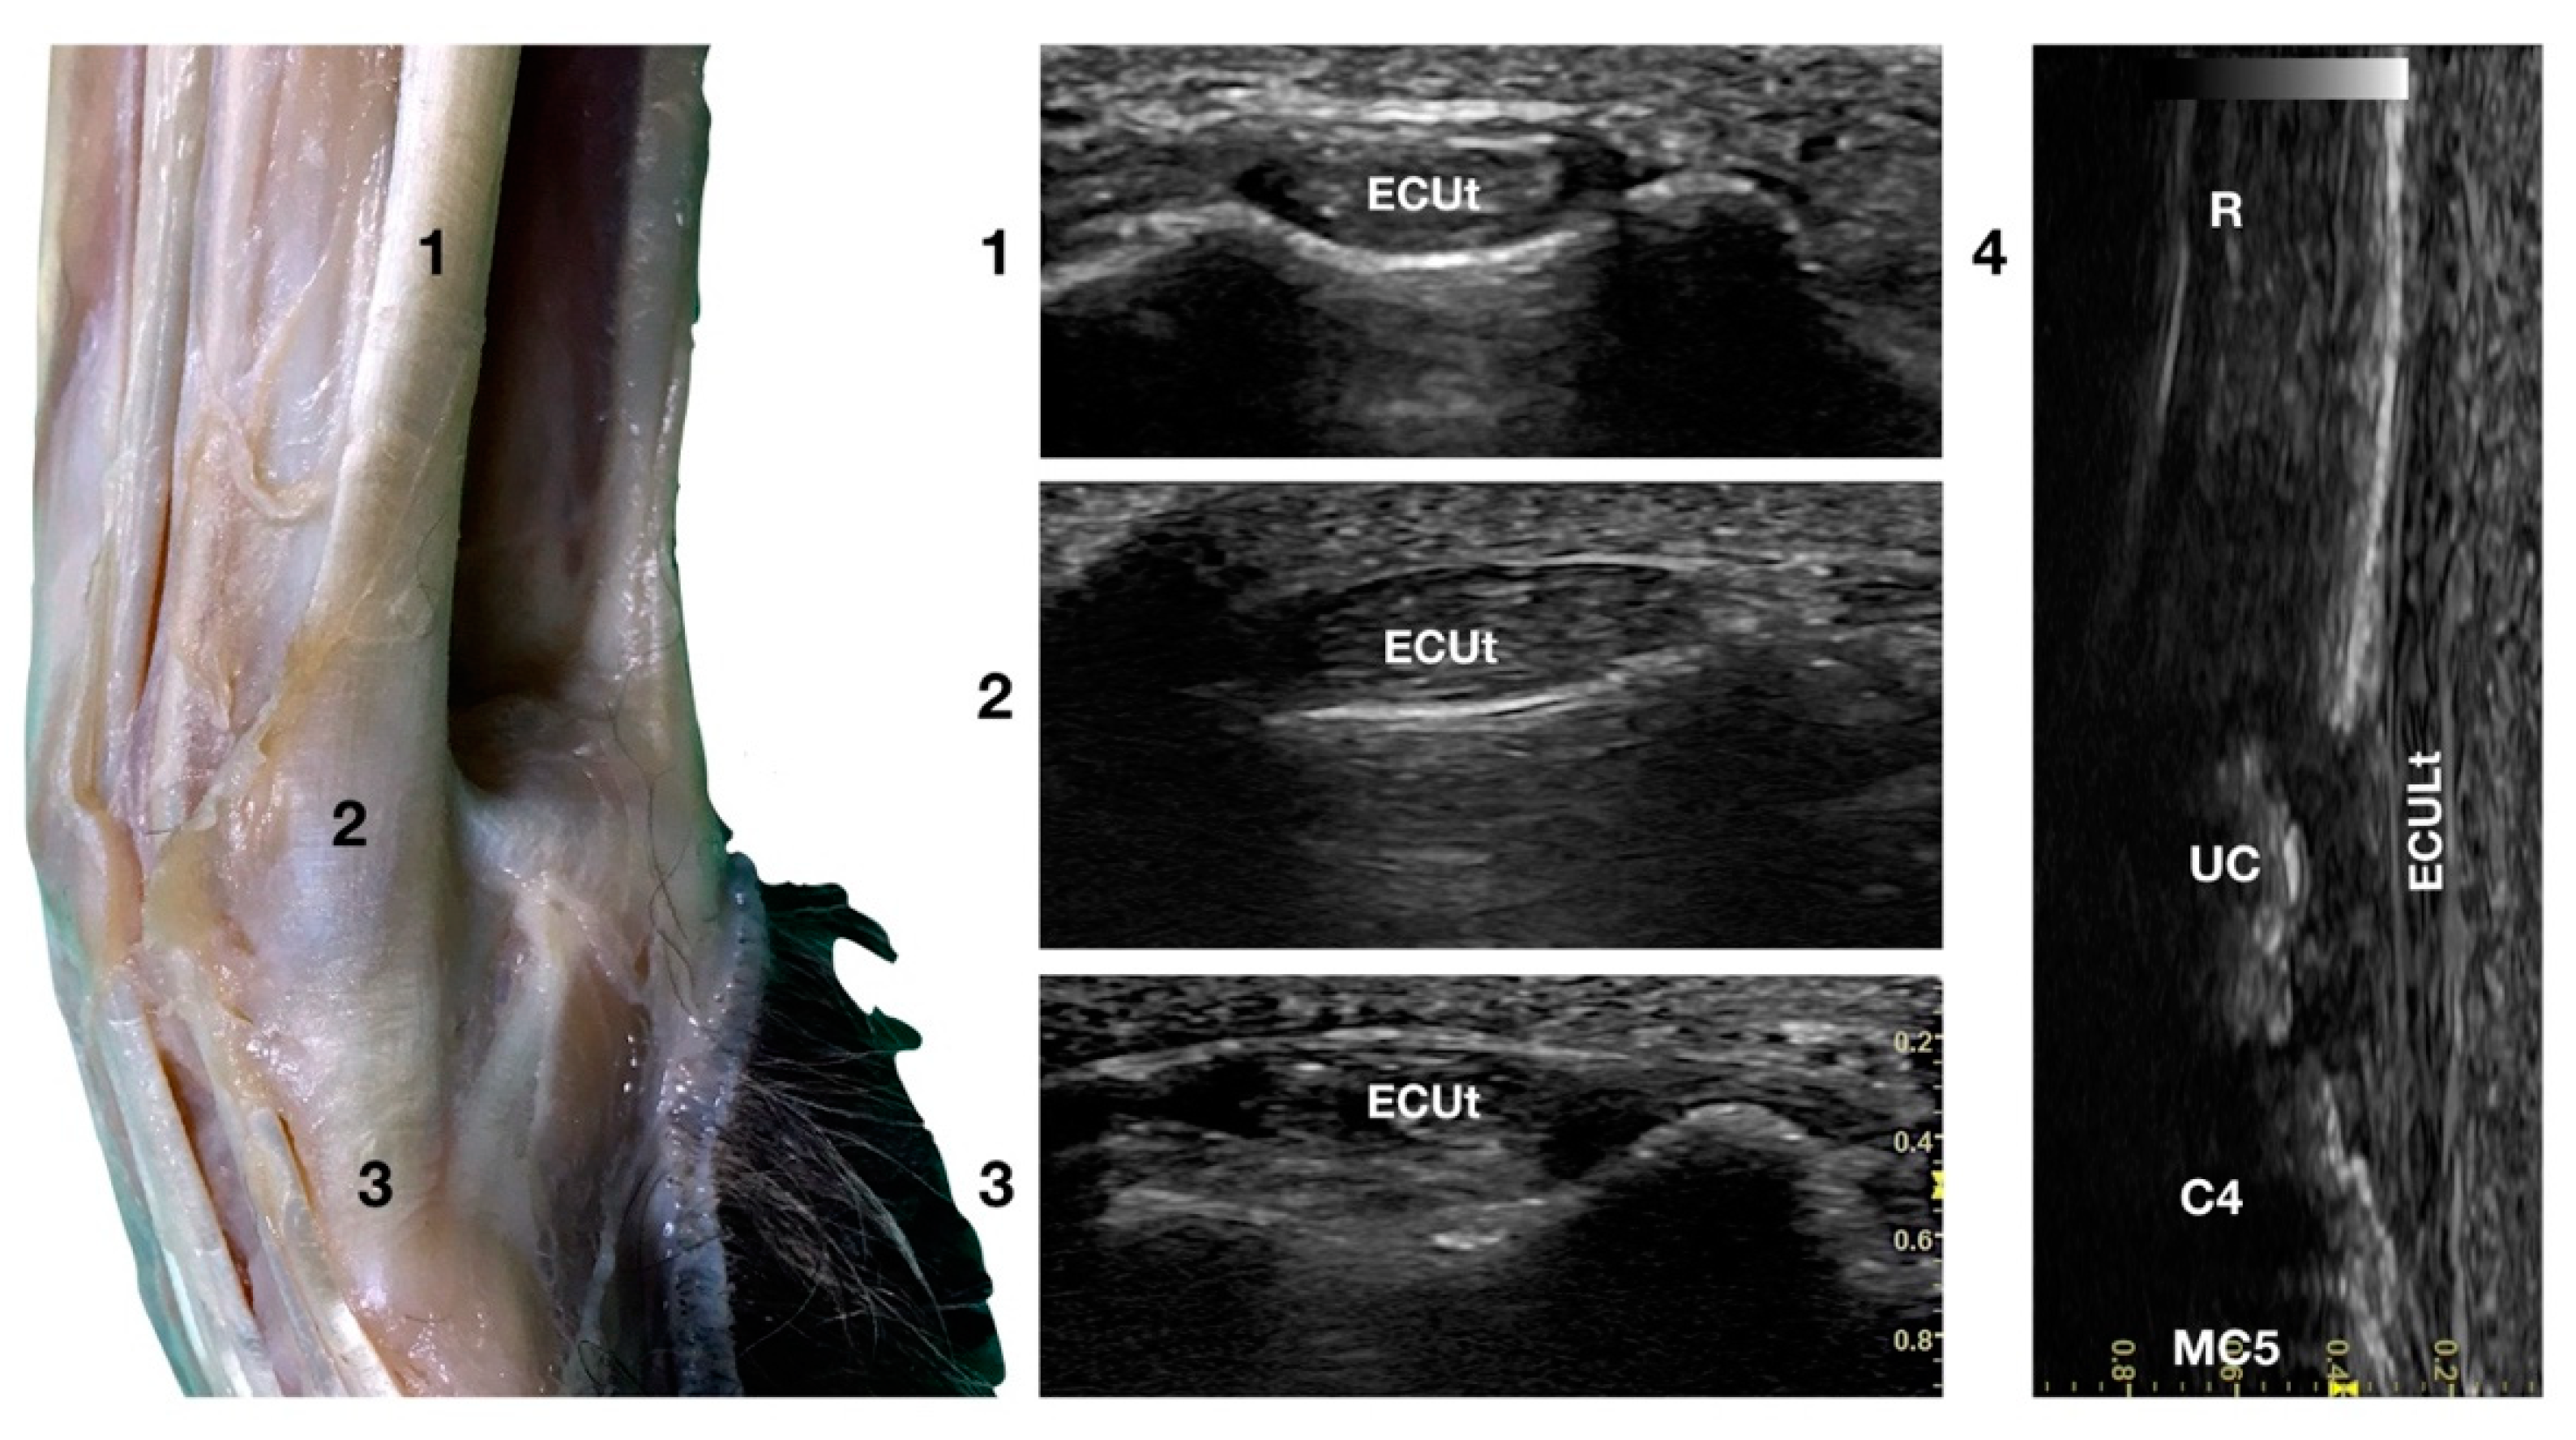

Extensor Carpi Ulnaris Tendon Ultrasonographic Anatomy (ECUt)

The large Extensor Carpi Ulnaris tendon (ECUt), also known as Ulnaris Lateralis tendon was easily palpated and recognised as the most prominent structure on the lateral surface of the carpus (Figure 1b). When palpated, the tendon was firm in a standing patient, resembling a bony structure. This was due to the tendon fibrillar density and to the fact that the tendon ran in close contact with the underlying bony surface. At the ulnar notch level, the tendon was recognised in the transverse plane, as quite a flattened and relatively hypoechoic structure, rich in thin hyperechoic foci, and surrounded by a hyperechoic line (peritendineum) (Figure 5).

Figure 5.

Lateral carpal face centred on the Extensor Carpi Ulnaris tendon. At the ulnar notch level (2), the ECUt is seen as a wide and flattened oval tendon in direct contact with the osseous surface. Proximally (1), the tendon is thick and narrow. The ECUt runs on the lateral face of the carpus and ends at the base of the fifth metacarpal bone where it reaches its maximum width (3). On the longitudinal scan plane (4), the prominent fibrillar pattern of the large tendon is visible. The osseous surface beneath is recognisable. R, radius; RC, radiocarpal bone; C4, fourth carpal bone; MC5, fifth metacarpal bone.

In the larger patients, a multilayer onion-like appearance was rarely evident; the tendon was more uniform and homogeneous in the smaller patients. Proximally, reaching the tenomuscolar junction, which was located in the middle region of the antebrachium, the tendon was thicker and less wide. From its origin, the broad tendon passed laterally over the carpus, being held in place by a thin, transverse, tendinous band, which attached the ECUt to the accessory carpal bone. The tendon showed a prominent overall hyperechogenicity with a dense fibrillar pattern in the longitudinal scan. The ECULt ended laterally at the base of metacarpal V, and widened toward its insertion, achieving its maximum size. The standing position optimized the fibrillar pattern visualisation due to optimal alignment on the longitudinal scan. Carpometacarpal flexion and extension, and elevation of the fifth digit were used to check the tendon for adhesion or reduced range of motion. Medial and lateral stress was assessed to check for tendon compliance. The dynamic examination was easier to carry out when the paw was elevated.